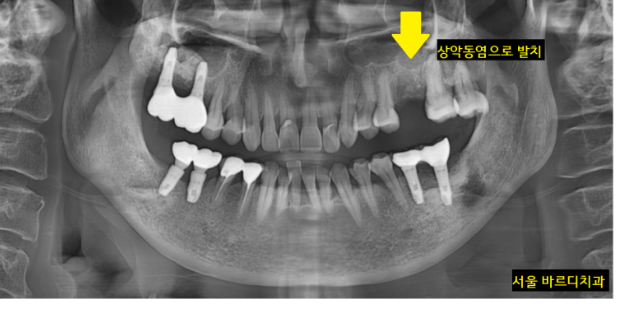

원인 파악을 위하여 전체 x-ray 촬영

역시나 왼쪽 윗니 치아에 문제가 있었습니다.

뿌리쪽에 문제가 있어보여

한 장 더 찍어보았는데요.

뿌리 끝에 염증이 발견되었습니다.

염증이 있어서 어금니가 아프셨던 거네요~~

치아에 염증이 있다 보니

주변 잇몸뼈를 녹은 상황

신경치료도 다 되어있는 상황이라

더 이상 치료할 수 있는 방법이 없었습니다.